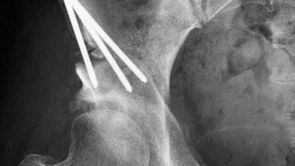

Our Hip Preservation Team brings together fellowship-trained surgeons with decades of combined experience in hip preservation and reconstructive surgery. Working collaboratively, our physicians perform some of the most advanced procedures in the country—including periacetabular osteotomy (PAO), hip arthroscopy, and complex reconstructive surgery. When you choose Panorama, you benefit from the combined expertise of a team that consistently delivers outstanding outcomes for patients with even the most complex hip conditions.